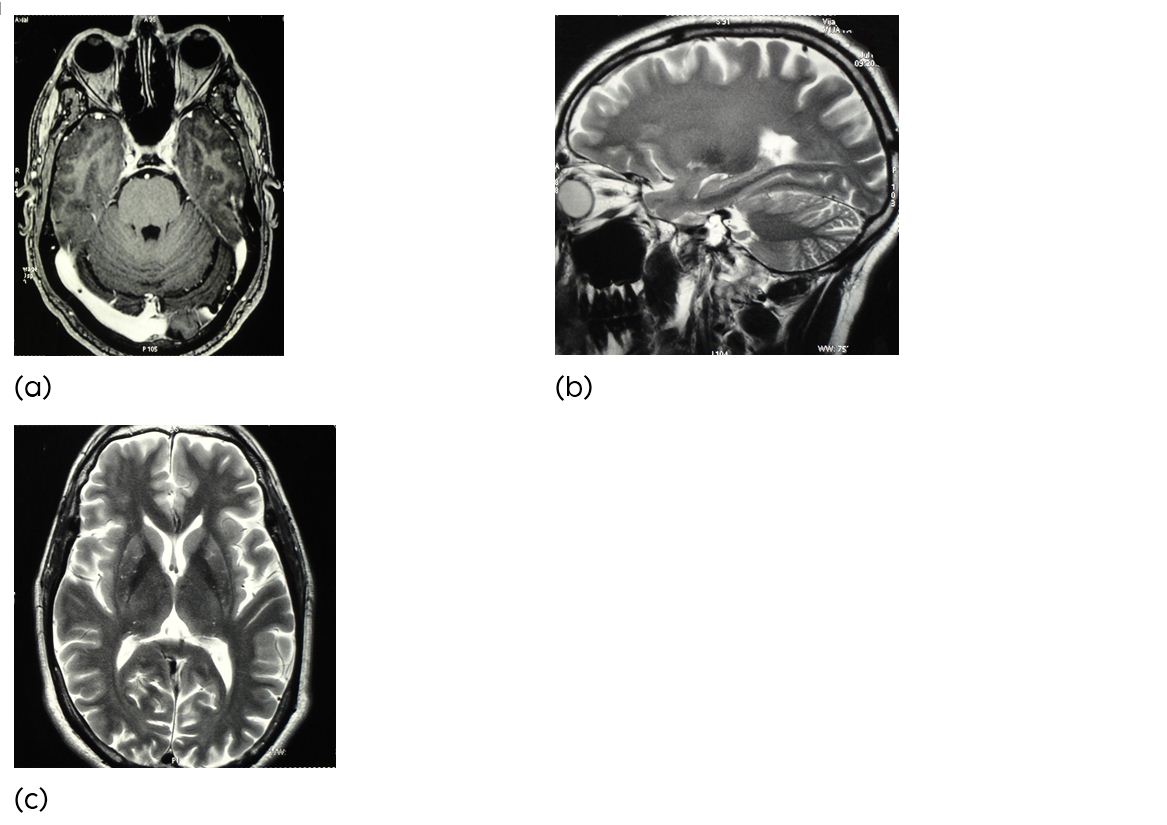

Case 2

A 48-year-old man was admitted because of sudden onset of a left hemiparesis associated with headache, nausea and vomiting with involvement of lower cranial nerve involvement. Bells approach brain MRI demonstrated an acute intrinsic pontine haematoma (Figure 2). Retromastoidal cranieoctomy sub occipital trans cerebellar approach was chosen. The pial surface of the brain stem showed hemosiderin laden changes in colour. Using MRI guided navigation, the bleeding cavity and the cavernous malformation were localised and the entry point on the pial surface of the brain stem was identified. After complete excision of the cavernous malformation, the bleeding cavity was inspected with the neuroendoscope to exclude remaining pathological vessels and to achieve sufficient haemostasis. After eight months of surgery the neurological examination showed a residual left hemiparesis, but the patient was able to walk independently (Rankin score 2).

Figure 2a,b,c: (a-c) Axial & Sagital MR image showing an acute pontine haemorrhage.